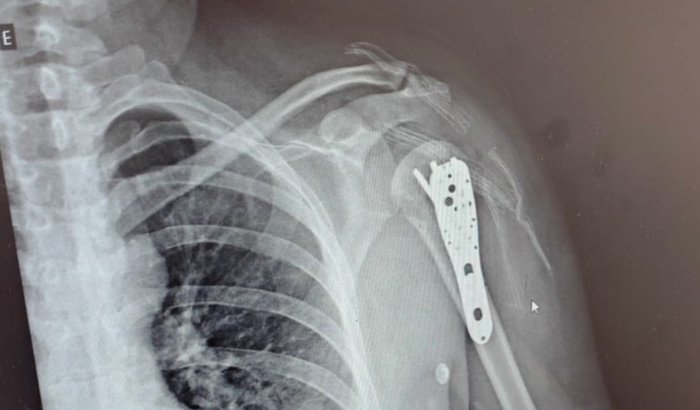

como muitos sabem, nossa querida Nete sofreu um grave acidente de moto que levou a uma delicada cirurgia e agora segue em recuperação, início de fisioterapia e o começo de um novo trajeto em sua vida.